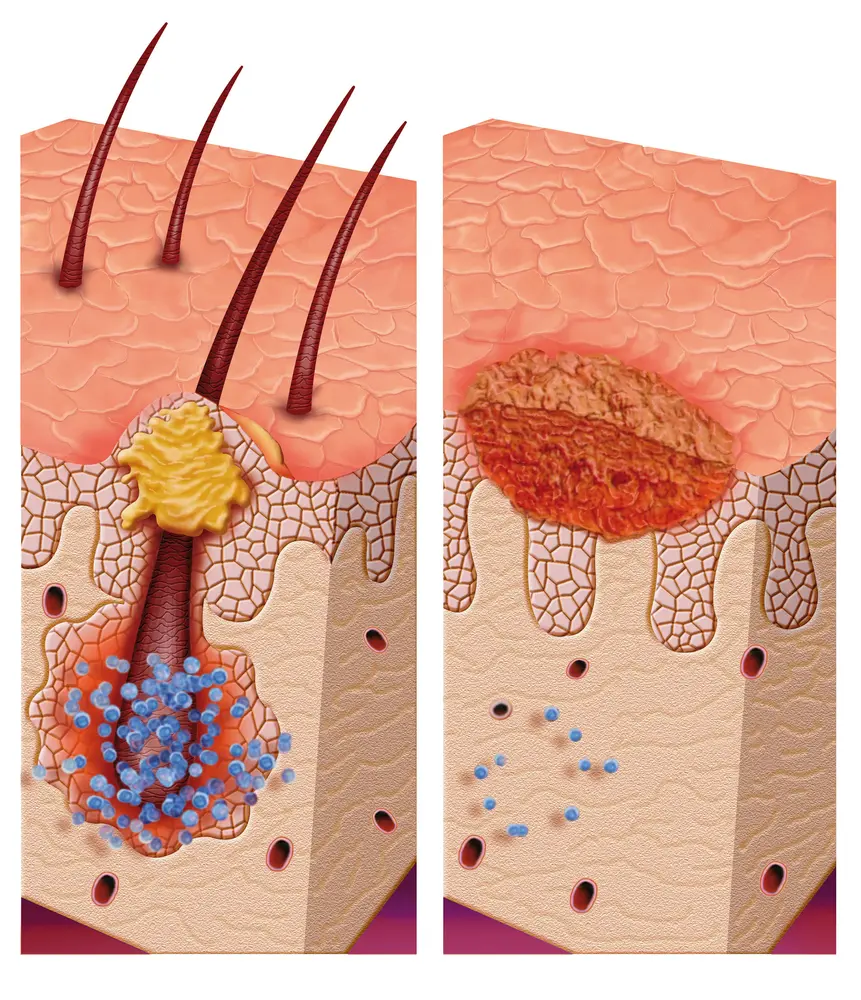

Acne can be caused by a build-up of oil and dead skin cells. If not addressed, acne can cause permanent scarring. Acne is most commonly caused by hormones, but it can also be caused by lifestyle choices, such as diet and stress. Naturopaths believe that the body can heal itself and that it focuses on restoring balance and harmony to the body’s internal system. They may recommend dietary changes, supplements, exercise, and natural care like aromatherapy or probiotics to help reduce acne symptoms.

Vulgaris is a condition that affects primarily adolescents and young adults. It is caused by an overproduction of sebum, which is a type of oil. Acne can be mild or severe, and can occur on any part of the body. The most common areas are the face, neck, chest, and back.

Naturopathy has been used as therapy for acne for years. Acne is caused by oil and bacteria accumulation on the skin. Naturopathic care work to correct the underlying cause of the acne, rather than just addressing the symptoms.

Acne is caused by a combination of factors, including overactive sebaceous glands, bacteria, and the buildup of dead skin cells.